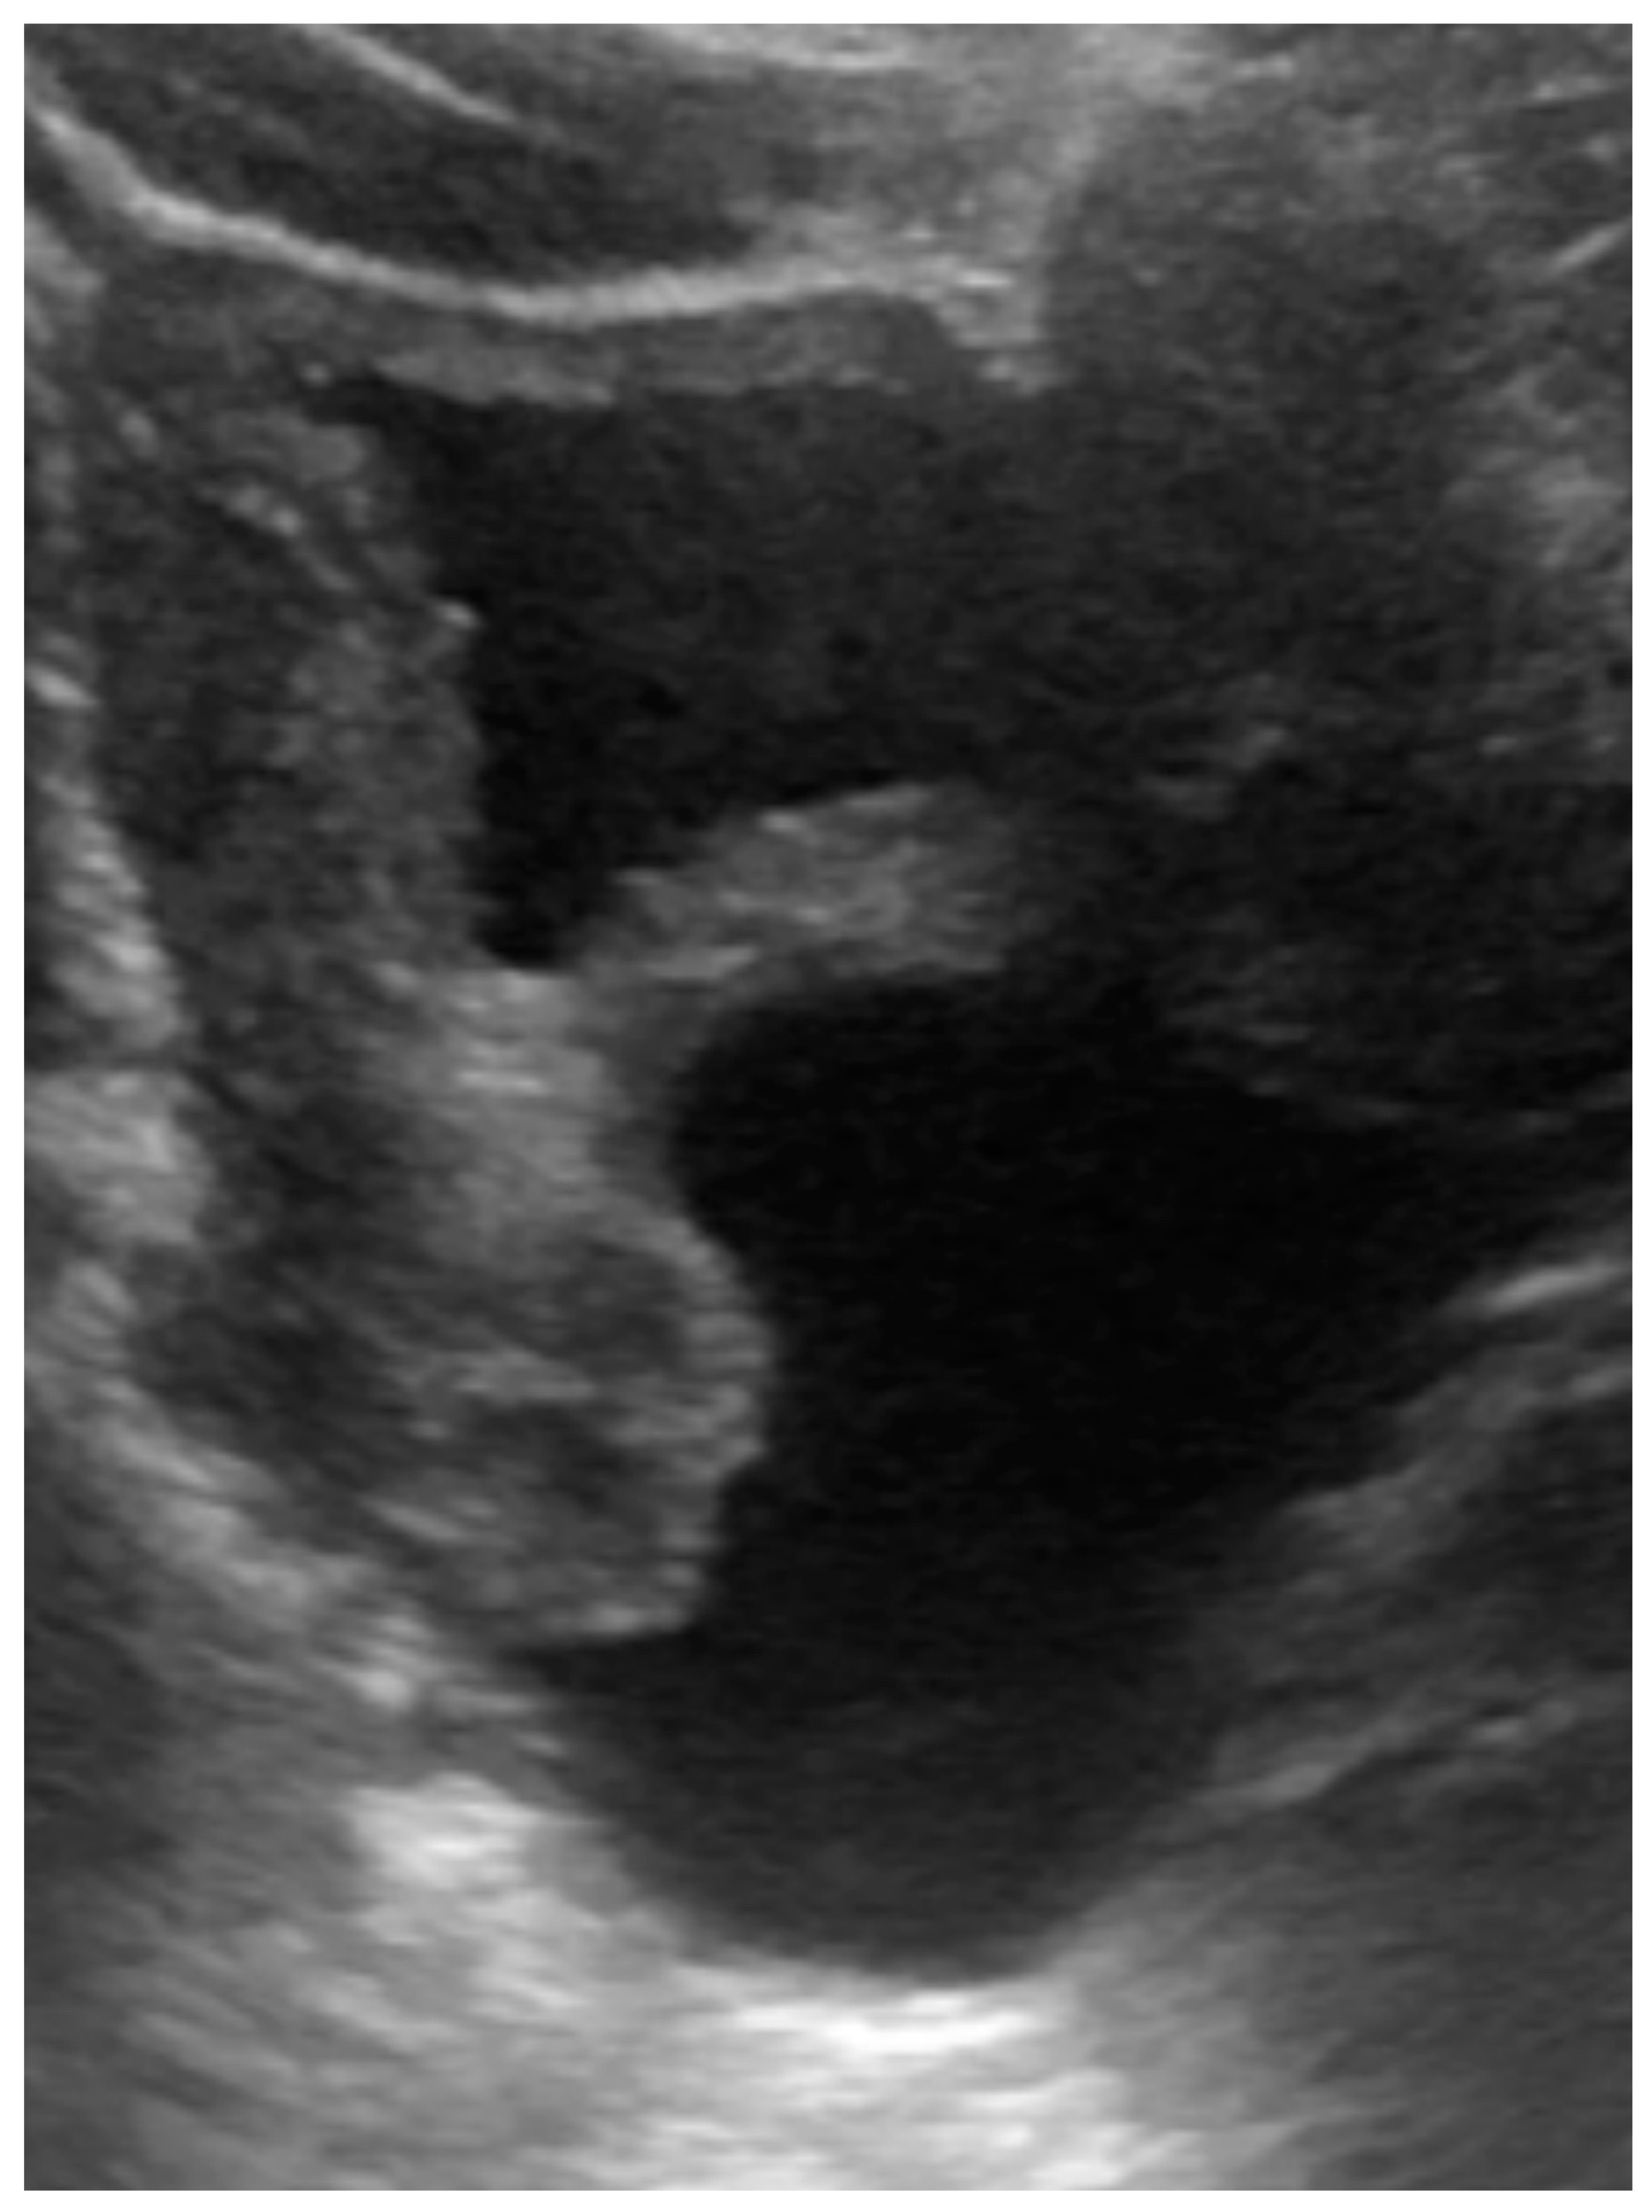

The patient presented with defecation difficulty at 2 months of corrected age. The ultrasound (Figure 3) and MRI demonstrated hydrocolpos, and presence of uterus and bilateral ovaries. Cystoscopy failed to identify the opening of the vagina. Currently, the girl is 8 months of corrected age with fair development and growth. Follow-up ultrasound still revealed hydrocolpos, but without compression effects. MRI examination will be arranged before puberty for further surgical correction.

Figure 3.

Ultrasound of case 2: hydrocolpos.